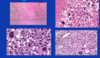

malignant pheochromocytoma

The only way we can know for sure if it’s malignant is if it’s metastasized. Otherwise they can show a lot of pleomorphism – see how big and dark these nuclei are. That’s not a helpful feature in endocrine organs as opposed to epithelial organs, where we expect cancer if we see this.

They can also have mitosis and vascular invasion and can even be found outside of adrenal (extra-adrenal paragangliomas).

You really have to prove metastasis to prove it’s malignant. In real life we try to apply several features including invasion of other organs, of vessels, if too many mitosis we may comment that the tumor has a higher malignant potential.